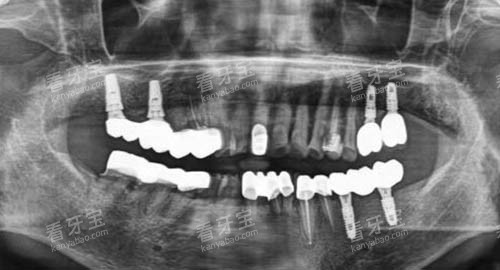

上海鼎植口腔在口腔种植领域拥有多项专有技术,这是其强大实力的体现。

其中,穿颧穿翼种植技术是鼎植口腔的一大特色。

对于一些牙槽骨条件较差、传统种植方式难以实施的患者来说,穿颧穿翼种植技术为他们带来了新的希望。

该技术通过将种植体植入颧骨或翼板等部位,无需进行骨增量手术,大大缩短了治疗周期,减少了患者的痛苦。

鼎植口腔的医生团队在穿颧穿翼种植技术方面有着丰富的临床经验,已经成功为众多患者解决了牙齿缺失问题,让他们重新拥有了健康的牙齿和自信的笑容。

此外,鼎植口腔还引进了可靠的智能化口腔诊疗技术。

智能化口腔技术可以实现口腔数据的比较准采集和分析,医生可以根据患者的口腔模型和数据进行个性化的治疗方案设计。

在种植手术中,通过智能化导板的引导,种植体的植入更加比较准、可靠,大大提高了手术的可行性和治疗结果。